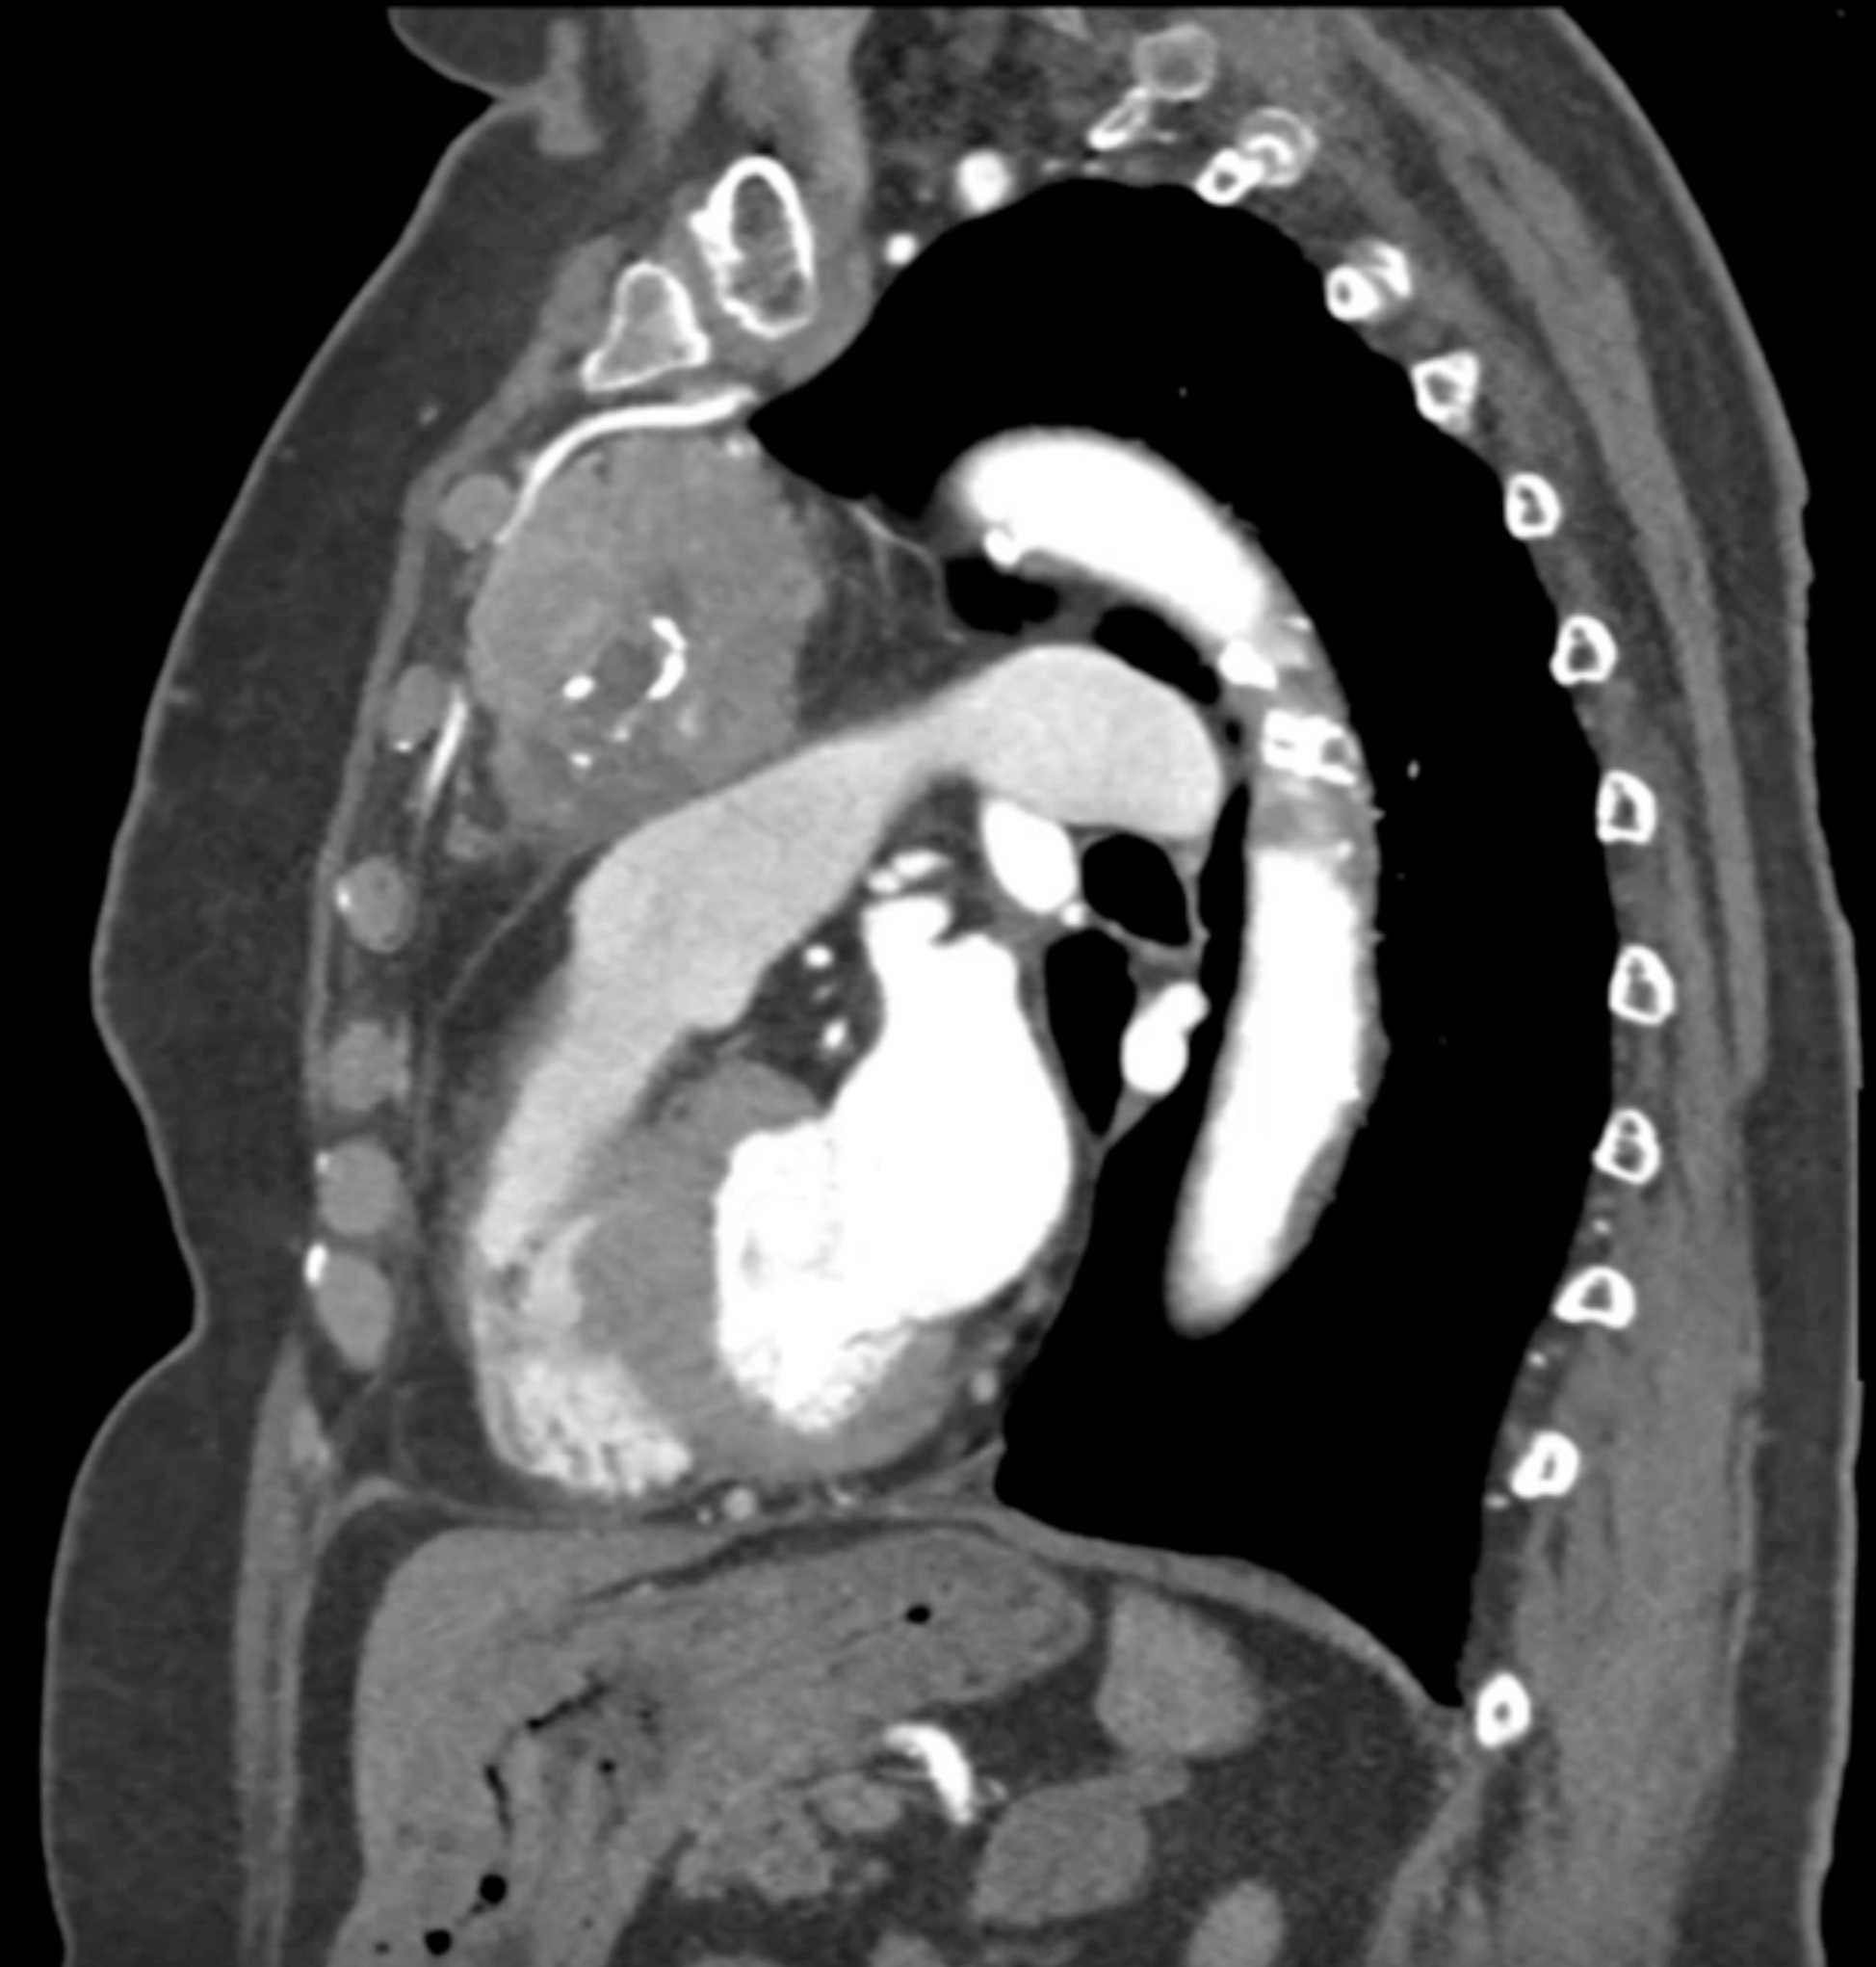

Thymic Carcinoma